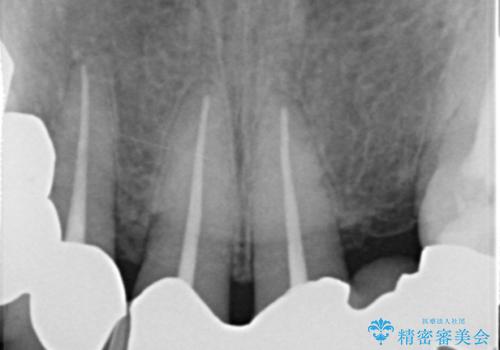

上の前歯6本はメタルボンドクラウン(内側が金属の被せ物)で補綴されており、顕著な歯肉退縮を認めました。

被せ物を除去したところ根管治療後の処置が不十分であったため、ファイバーコア(金属を用いない強くてしなやか材質の土台)を植立したのち、ジルコニアセラミッククラウンによる治療を行いました。